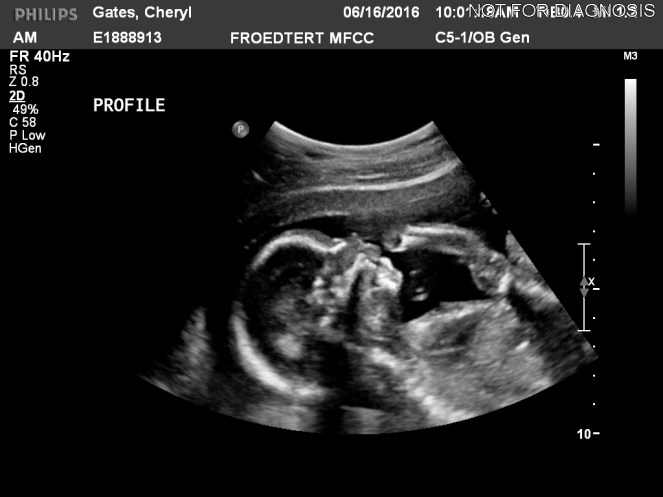

Dude we are HALFWAY through this pregnancy madness! Seriously unbelievable how fast it is going. Our 20 week ultrasound went great. Baby was squirming around like an inchworm – the poor tech had the hardest time getting good shots. It also had hiccups, it was hilarious! It already has its own agenda and will answer to no man, or camera. Way to go, baby!

Being the conditioned catastrophic thinker that I am, I had been having nightmares about the baby looking more like the sea animals I describe it as than as an actual baby, so seeing it up on the big screen again gave me major reassurance that we are not, in fact, growing a crop of squids in there. Doc said all is looking well on the medical side of things, and the little baba is weighing in at about 11 oz – right at the 50th percentile for its underwater age. They were also able to spot the piddlybits that prove if this is a gentleman or lady starfish, and we covered our eyes when directed so we are still in the dark on that issue. Much like the transphobic must feel when they find themselves mid-pee and someone comes in and uses the stall next to them at Target.

Speaking of demons, the creature inside of me is alive and kicking, literally. The tap, tap, tapping I felt around 18 weeks but couldn’t say for sure wasn’t just Pamplemousse gas blossomed into a full blown punching/galloping situation around 19 weeks and hasn’t slowed down since. There is something super bizarre/comforting/awesome about feeling the literal miracle of life bopping around in your innards. Sir or madam Gates seems to be the most frolic-y after a good old fashioned sugar bomb snack, (or my current liquid of choice – root beer!) but really I can feel him/her/it taking my uterus by storm at all hours of the day. Gates was able to feel a little roundhouse for himself around 20 weeks, and that was probably my favorite moment of all the pregnancy fun we’ve had thus far.